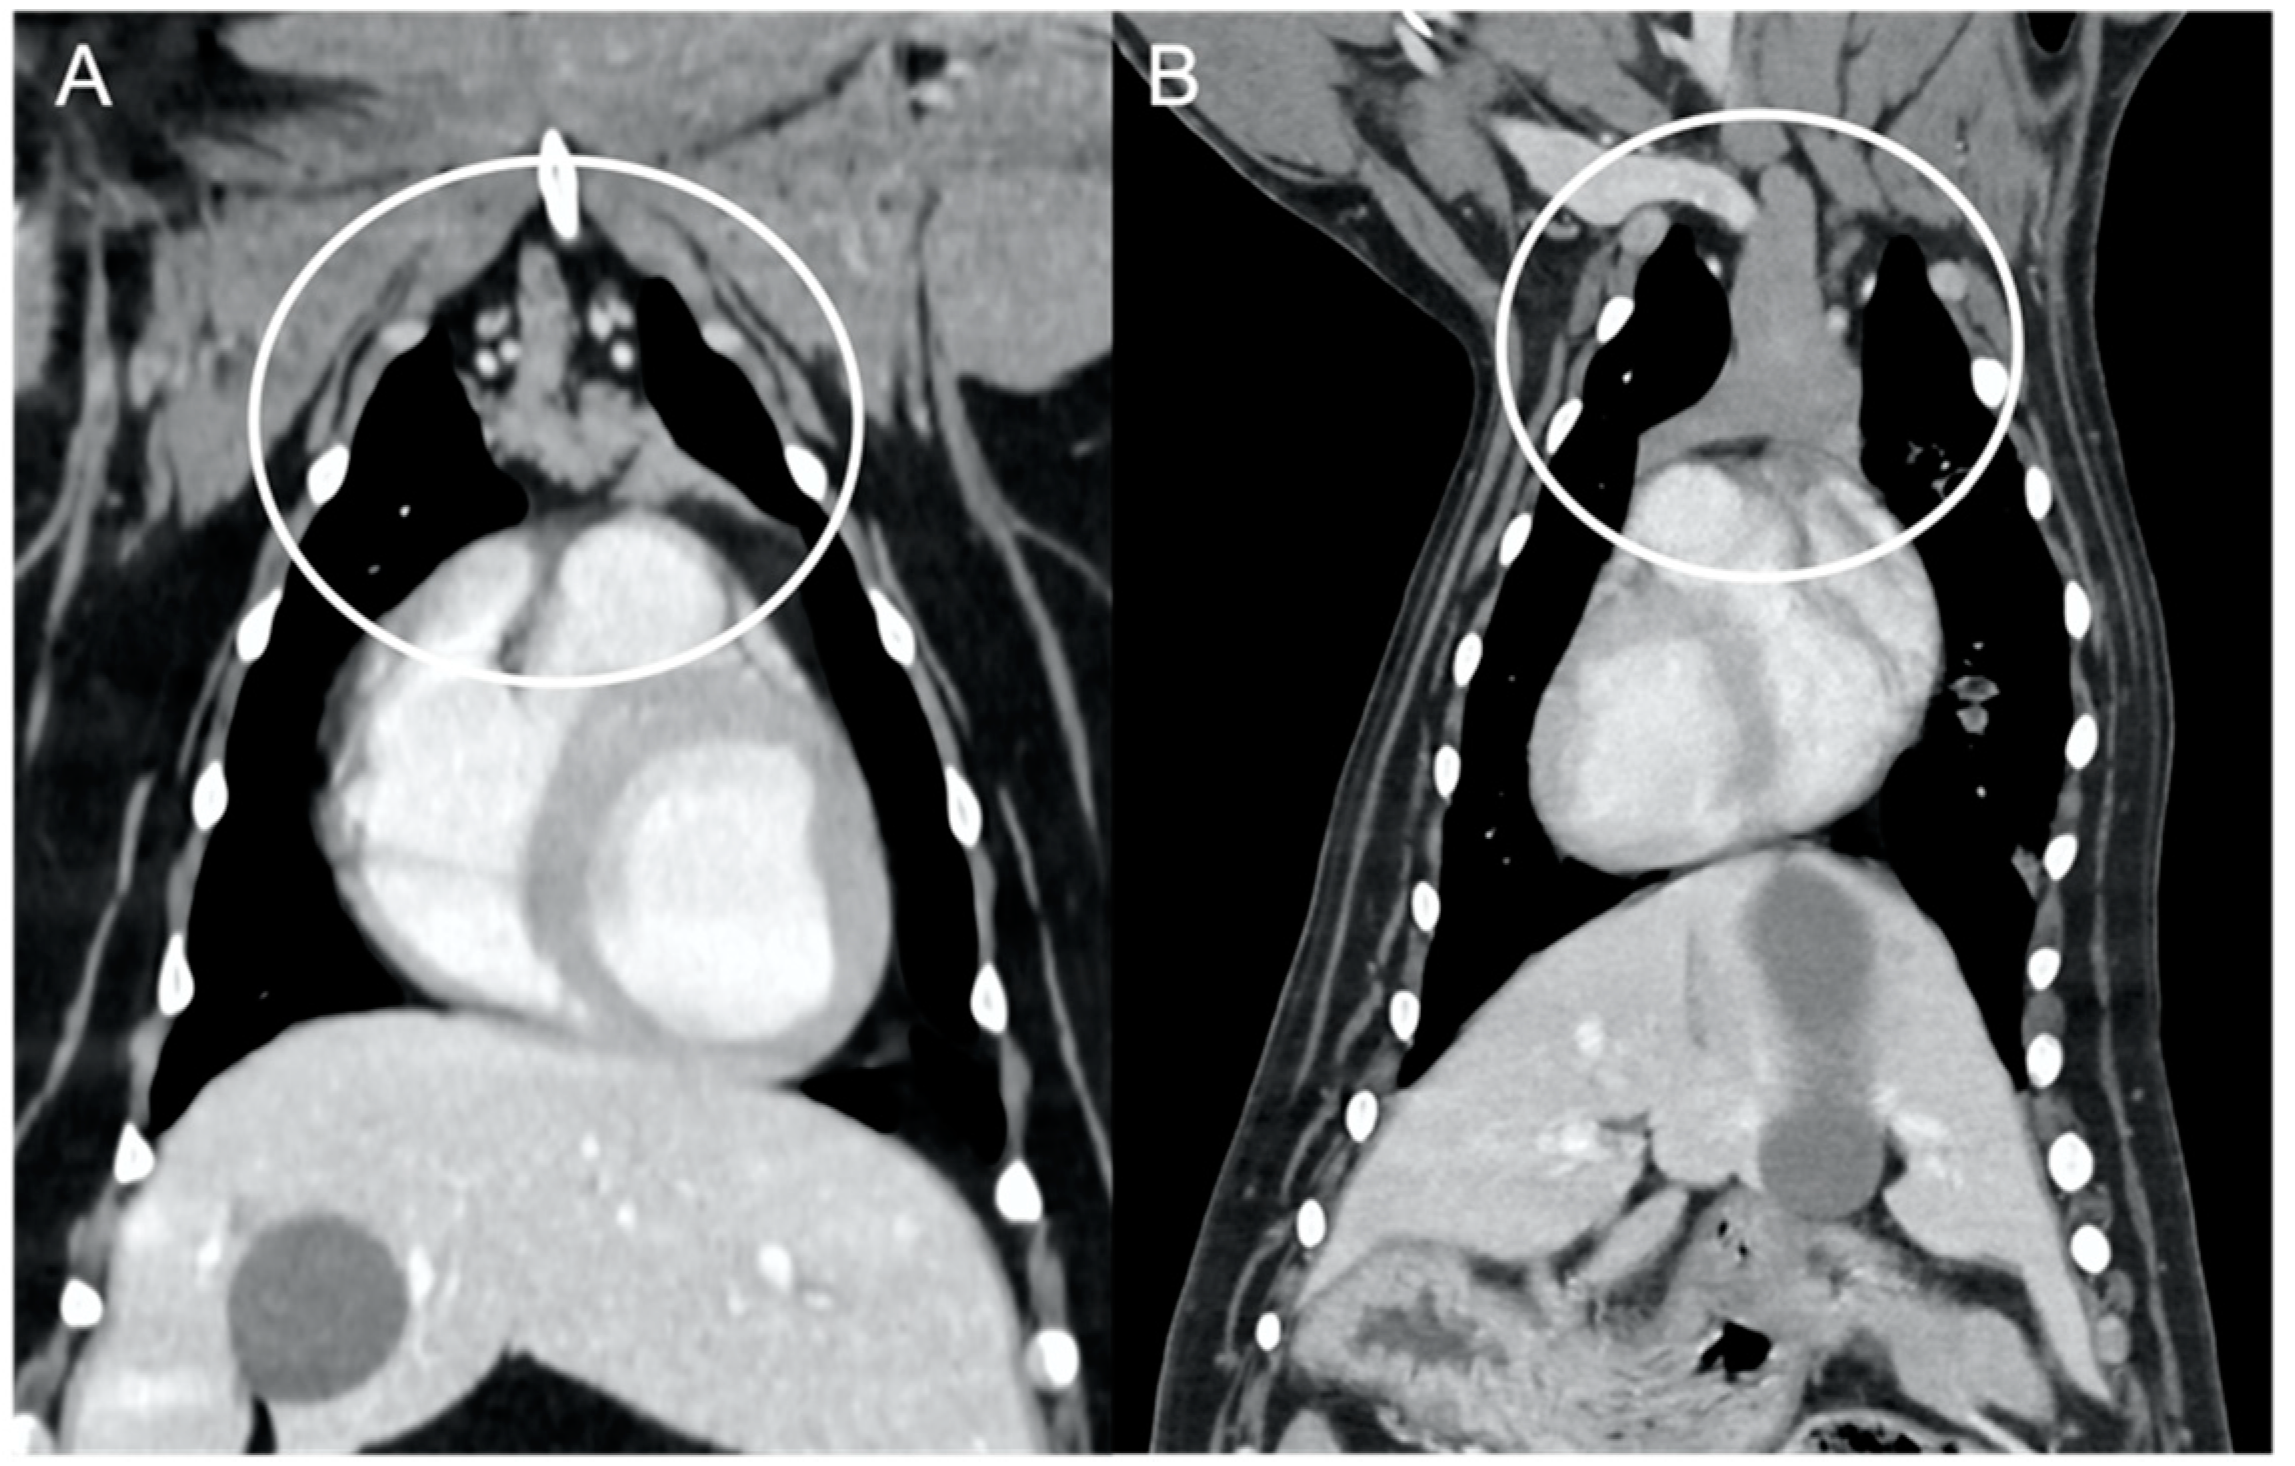

The overall appearance was lobulated in all of the adult dogs and homogeneous in all of the juvenile dogs (Figure 1 and Figure 3). The thymus was left-sided in all of the adult dogs, while it was located in the midline in a few juvenile dogs; one presented a thymus on the right side due to situs inversus (Figure 4). The maximum dimension of the thymus in the adult dogs group was always the length, while in some juvenile dogs, the maximum diameter was the width (Figure 2). The dimensions of the thymus were variable between different patients, with several breeds included and large differences in body weight between the dogs. For this reason, a ratio between the maximum diameter of the thymus (measured in cm) and the body weight (measured in kg) was calculated for each dog. The median ratio in the adult dogs group was 0.2 (minimum: 0.06; maximum: 0.4), while in juvenile dogs, it was 0.4 (minimum: 0.1; maximum: 1.4). The dogs with the higher ratio (>1) were in the juvenile group and they presented with spinal a cyst and enteritis and were 6 and 7 months old, respectively. The dogs with the lower ratio (<0.1) were in the adult group and they presented with muscular hemangiosarcoma (one dog) and synovial cell sarcoma (two dogs) and were 2, 6, and 8 years old, respectively.

The thymus was less attenuating in adult dogs compared to young dogs, with a median of the mean pre- and post-contrast attenuation values lower in adult dogs compared to juvenile dogs (Table 1). In 5/11 (45%) adult dogs, the minimum pre-contrast attenuation values were negative values (from −22 to −2 HU), due to the presence of multiple, hypoattenuating, thick septi within the thymic parenchyma (Figure 5).

Several CT features of thymic neoplasia have been described in dogs. Thymomas have been described as large, space-occupying masses arising from the cranial mediastinum, frequently heterogeneous or with a cystic appearance, mainly left-sided but being more centrally located with increasing size [6]. Vascular invasions have been reported, especially in larger masses [6]. Cranial mediastinal lymphomas have been described as more homogeneous masses compared to thymic epithelial neoplasms, more likely to envelop the cranial vena cava [7]. The CT characteristics of thymic neoplasia reported in these previous studies, such as large masses, heterogeneous, enveloping or invading the adjacent vasculature [6,7], were significantly different from the findings of the current study, in which the thymus was in fact considered non-neoplastic. The CT appearance of thymic hyperplasia in humans can be variable, but some features, such as bipyramidal morphology and the presence of gross intercalated fat (also described as ‘marbling’), are considered pathognomonic [20]. This appearance of ‘marbling’, with the presence of several hypoattenuating septations throughout the thymic parenchyma, was present in all of the adult dogs included in the current study, suggesting that these dogs may have presented with thymic hyperplasia at the time of CT examination.

Figure 4. Lateralization of the thymus (circled) in two dogs. Post-contrast dorsal CT reconstructions. A mainly left-sided thymus in an adult dog (A) compared to a mainly right-sided thymus in a young dog (B) with situs inversus.

Figure 5. Appearance of the thymus (circled) in an adult dog. Post-contrast transverse CT image (A) and dorsal reconstruction (B). Note the presence of multiple hypoattenuating septi within the parenchyma, giving the thymus a lobulated appearance and overall low attenuation.